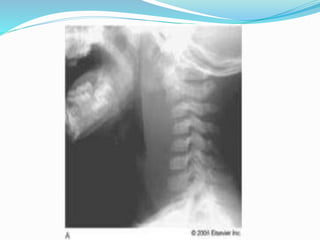

 CERVICAL : RETROPHARYNGEAL / AT POST

BORDER OF STERNO MASTOID IN POST

TRIANGLE OF THE NECK / AT AXILLA

 RETROPHARYNGEAL ABSCESS

RETROPHARYNGEAL ABSCESS

 RETROPHARYNGEAL

SWELLING

CAN PRESENT AS

DYSPHAGIA